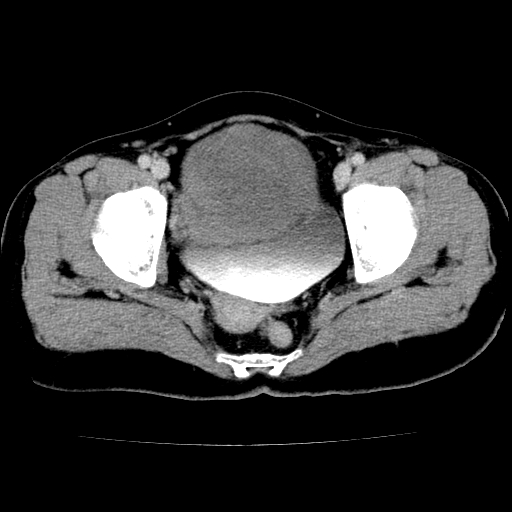

标题: CT24785:女,62岁,发现下腹部肿物半年。

女,62岁,发现下腹部肿物半年,下腹部不适。

老年女性患者,盆腔囊实性占位,ct增强不均匀强化,未见壁结节,未见腹水及盆腔积液,考虑附件囊腺瘤可能性大!